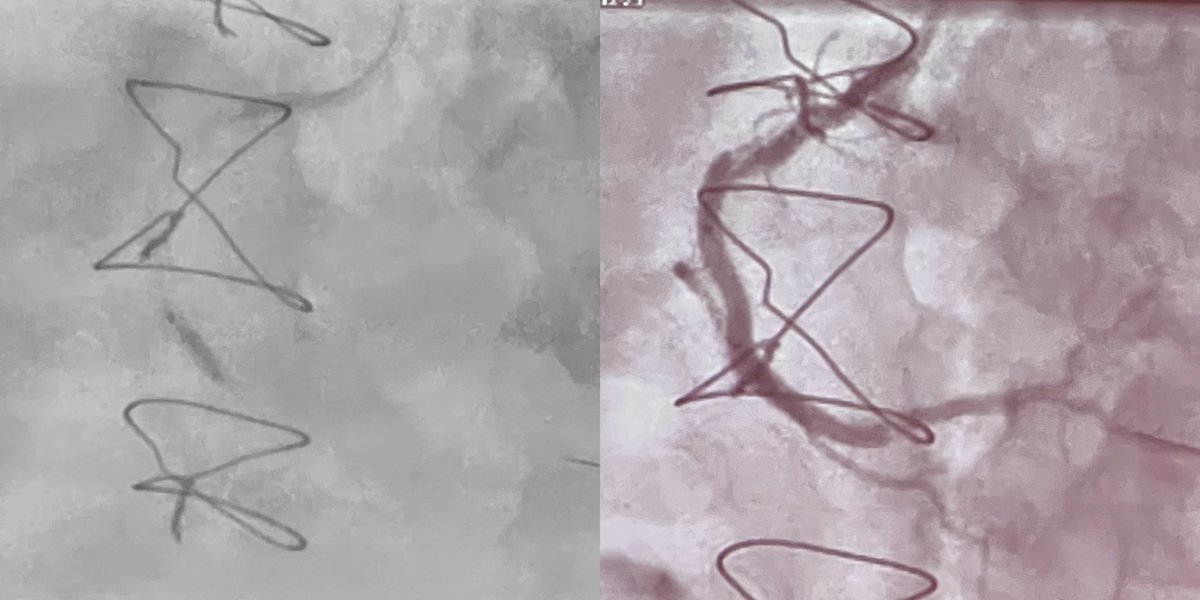

Check out the before and after images of this HD #IVUS guided #RotaShock PCI to optimize deployment of a 3.00x38mm SYNERGY XD. Congrats to @DoctorMoussa of @VirtuaHealth on successfully opening this heavily calcified LAD, making for a great #ComplexPCI case!